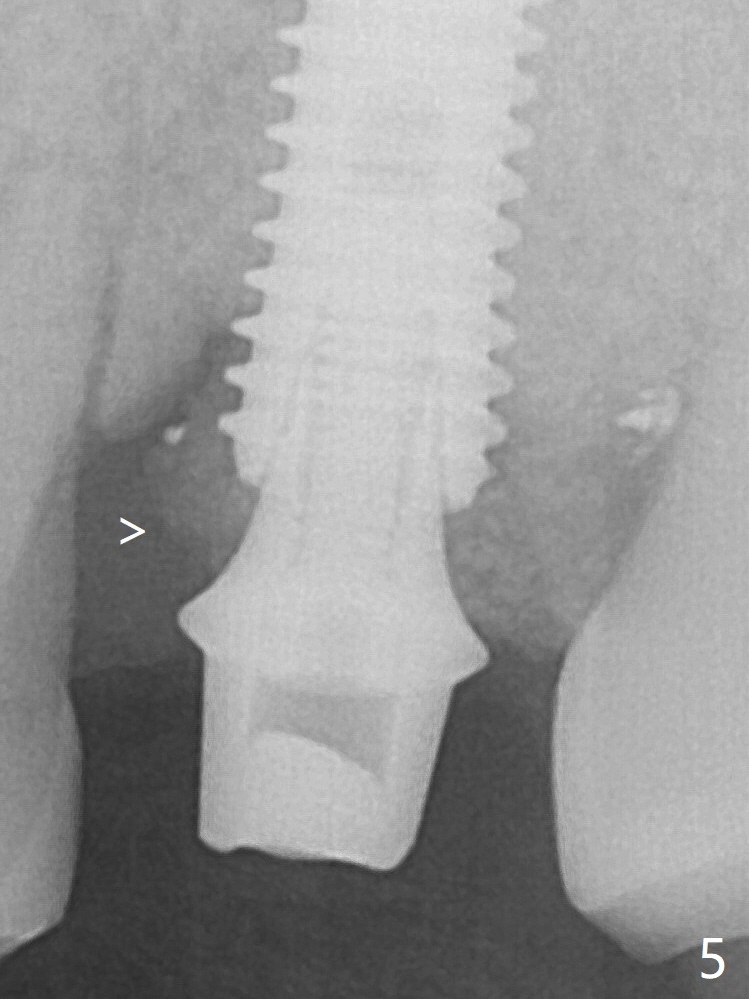

Further pushing of the bone graft from the buccal and palatal socket gaps results in more ideal packing (Fig.5 >). If the bone graft were placed first, packing would have been easier. An immediate provisional is fabricated to prevent further mesial shifting of the 3rd molar (Fig.1 arrow). The implant remains stable, while the provisional and abutment are loose 3 months 1 week postop (Fig.6). Impression is taken after abutment cleaning and retightening.